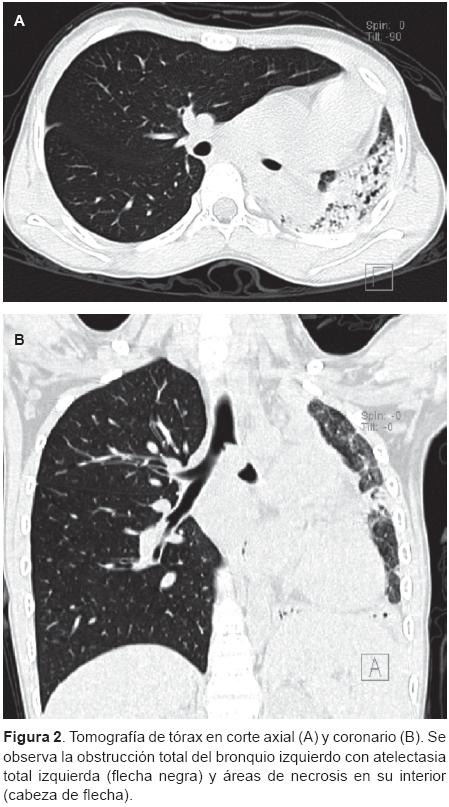

Se trata de una paciente de sexo femenino, escolar de 10 años de edad, previamente sana, quien desde el 2008 ha presentado infecciones recurrentes en vías aéreas (IRVA), y dos veces fue hospitalizada por neumonía en el pulmón izquierdo. Es conocida por nuestro servicio desde junio del 2011. Fue referida por IRVA, con episodios ocasionales de hemoptisis. Se inició el abordaje descartando causas comunes de IRVA, como sinusitis, inmunodeficiencia, fibrosis quística, entre otras. Se realizó una radiografía de tórax y se encontró atelectasia total izquierda con área de consolidación basal izquierda (Figura 1). Inicialmente, se manejó con antibióticos, esteroides, broncodilatadores, pero no presentó mejoría, y persistía con atelectasia total. Se realizó una tomografía axial de tórax (TAC) de alta resolución, en la que se observó estenosis del bronquio izquierdo, necrosis pulmonar izquierda, áreas de bronquiectasias y fibrosis (Figura 2). Posteriormente, se complementó el abordaje con una fibrobroncoscopia. Los hallazgos en el bronquio izquierdo fueron los siguientes: masa de color rojiza, no definida, granulomatosa, sólida, que ocluía completamente la luz del bronquio izquierdo y no permitió el paso del broncoscopio (Figura 3). La biopsia de la lesión reportó granuloma de bronquio izquierdo. Se realizó un estudio de gammagrama pulmonar ventilatorio/perfusorio que mostró datos de ausencia funcional del pulmón izquierdo y pulmón derecho con perfusión y ventilación normal, por lo que se practicó neumonectomía total. El reporte patológico final determinó lo siguiente:

La manifestación radiológica más común es la presencia de una masa intraluminal en el árbol traqueo-bronquial, aunque es difícil predecir su situación endobronquial cuando se encuentra en bronquios segmentarios. La lesión pulmonar secundaria a la obstrucción, como la atelectasia presentada en nuestra paciente, se encuentra en la tercera parte de casos.13,14. En la TAC de tórax puede aparecer como una masa de bordes bien definidos, de forma oval o lobulada, con calcificaciones puntiformes en la mitad de los casos y con reforzamiento leve con el medio de contraste. La dirección del diámetro mayor del tumor es paralela a la dirección de ramificación de la vía aérea en la que se encuentra.1,2 En este caso, no se observó ninguna masa bien definida, solamente estenosis del bronquio principal izquierdo, atelectasia total izquierda y necrosis pulmonar izquierda secundaria a los eventos de neumonía previos. Por esta razón, se decidió realizar la exploración endoscópica, que corroboró la presencia de una masa que ocluía todo el bronquio izquierdo. Se llevó a cabo la biopsia y, posteriormente, se programó para neumonectomía. De aquí la importancia de realizar el estudio endoscópico para el abordaje de estos pacientes.4,11